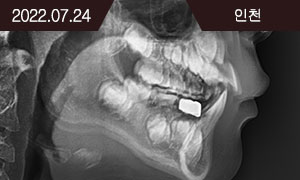

Face-mask를 이용한 골격성 III급 부정교합의 악정형치료

치료 과정

AFTER

2021.12.22